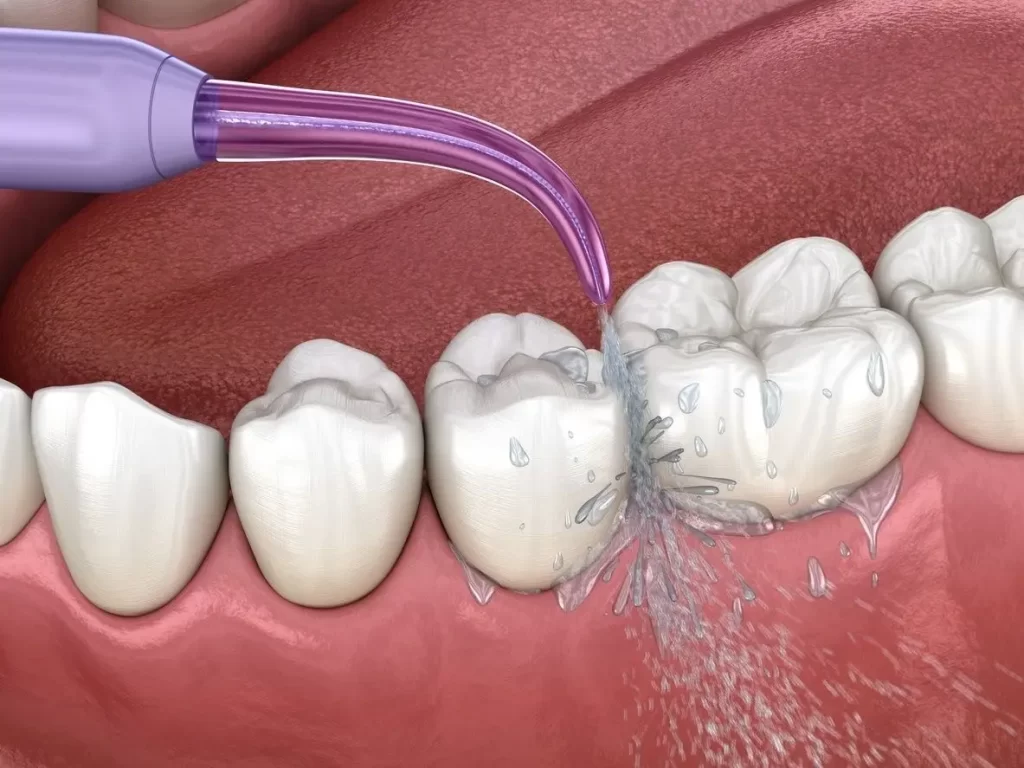

Desni su ogledalo zdravlja. Zdrave desni su ružičaste boje,čvrste na dodir i ne krvare. Predstavljaju temelj i potporu zubima u njihovoj funkciji žvakanja. Bolest desni može ubiti mnogo više od Vašeg osmeha. Sve počinje crvenilom i krvarenjem desni, nastavlja se njihovim povlačenjem a završava rasklaćivanjem i ispadanjem zuba.

Parodontologija se bavi prevencijom bolesti potpornog aparata zuba kao i rešavanjem postojećih parodontoloških problema. Parodontalni džep je tvorevina koja se javlja kada bolesne desni zahvate i dublje slojeve potpornog tkiva koje kreću sa laganim povlačenjem. Svi smo nekada čuli za problem osećaja zapadanja hrane između zuba i neprijatnog mirisa koji za sobom ostavlja.

Zdrave desni su privilegija koju bi trebalo sebi da priuštite.

Na prvi znak bolesti potpotnog aparata zuba treba pravovremeno reagovati odlaskom kod stomatologa.